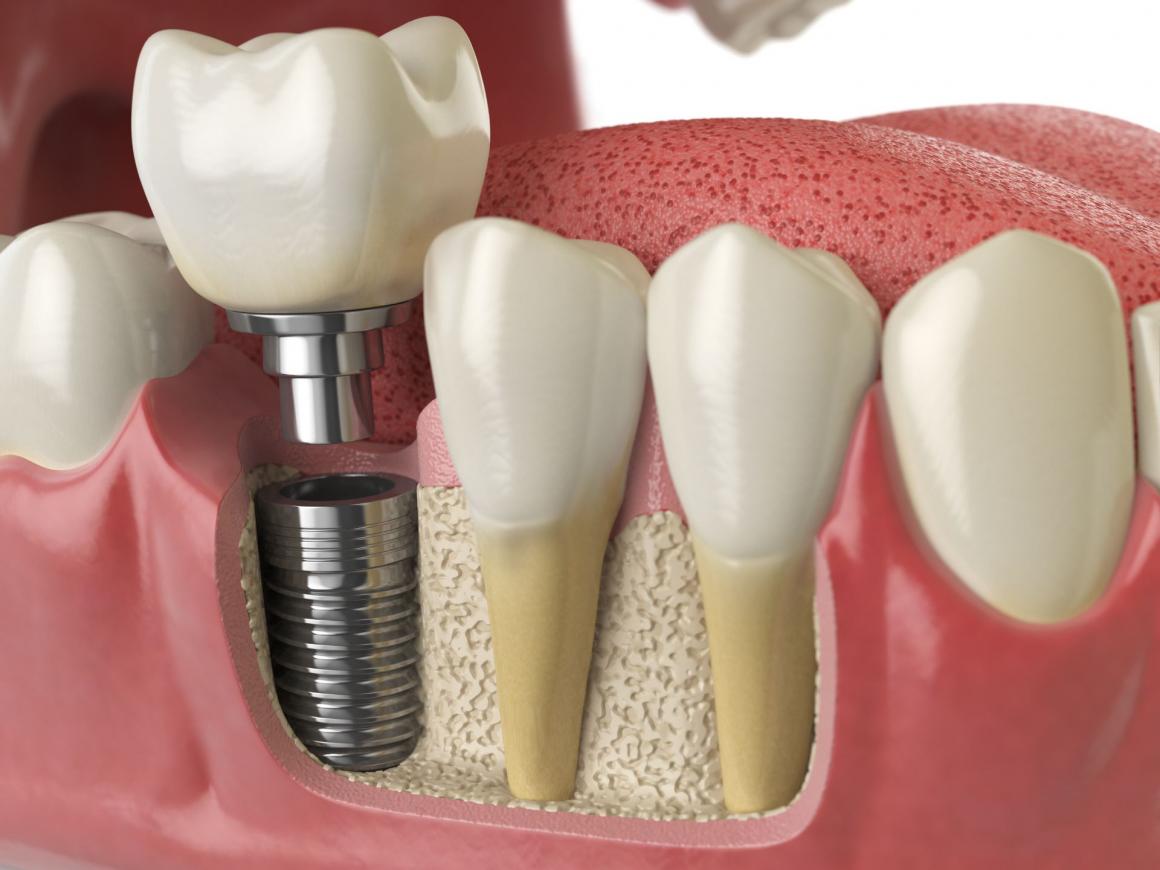

Der im Kiefer implantierte Teil ist schraubenförmig oder zylindrisch geformt. Der zweite Teil - der Implantatpfosten - wird später eingeschraubt und bietet dem Zahnersatz einen festen Halt.

Die Form des Implantatpfostens wird durch die Art des Zahnersatzes und die Position des Implantats bestimmt. Die äußere Form des Implantats richtet sich nach den individuellen Kieferverhältnissen, dem Ort der Anwendung und seiner Aufgabe als Wurzelersatz.

Alle Implantate haben eine strukturierte Oberfläche, um die Einheilphase zu verbessern, und einen hochglanzpolierten Implantathals, damit sich der Zahnfleischrand gut anlegt.

Einzelzahnersatz

Der Verlust einzelner Zähne lässt sich durch Implantate gut ausgleichen. Die künstliche Wurzel gibt dem Zahn einen sicheren Halt. Die Nachbarzähne müssen nicht wie bei einer Brücke beschliffen werden.